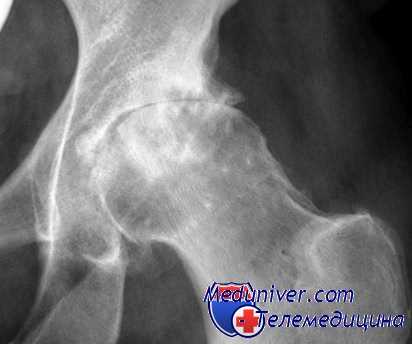

Рентгенологическое исследование

Стадия коксартроза устанавливается проведением рентгенографического исследования. На полученных изображениях отчетливо просматриваются деструктивные изменения в тазобедренном суставе. Это сужение суставной щели, деформация костных поверхностей, формирование остеофитов.